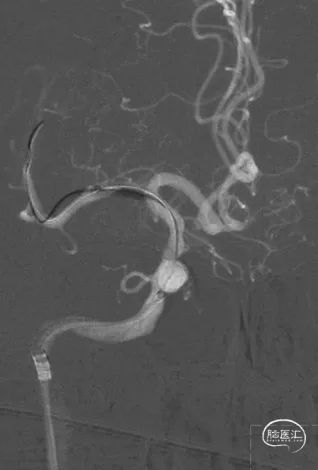

释放球扩支架(2.5*10mm)。

球扩支架后,造影显示仍有部分血管弹性回缩。

再次球囊扩张。

球扩后造影。

➢ 术后影像

术后造影。